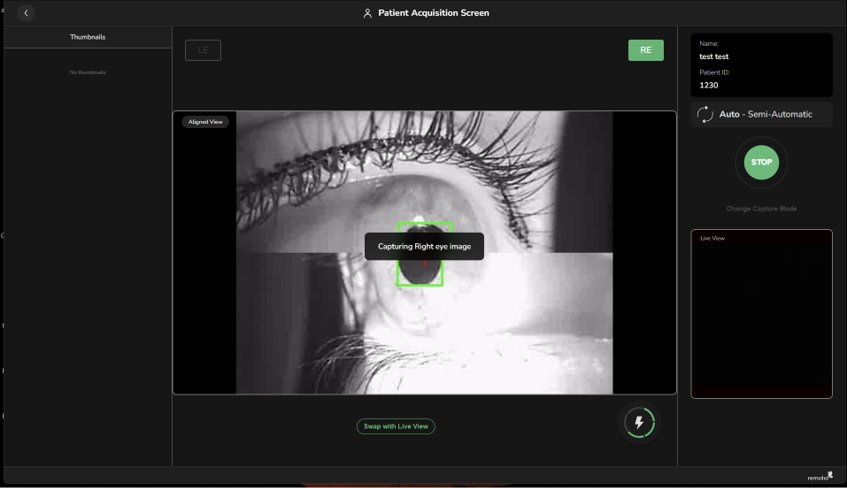

Laser autofocus, auto-pupil tracking and two different image modalities ensuring faster capture

Laser autofocus, auto-pupil tracking and two different image modalities ensuring faster capture

Automated image acquisition enables rapid retinal imaging with minimal training and reduced operator dependence

Just hold the device in place and choose an eye segment. The FOP will automatically capture an image for you - its as easy as that.